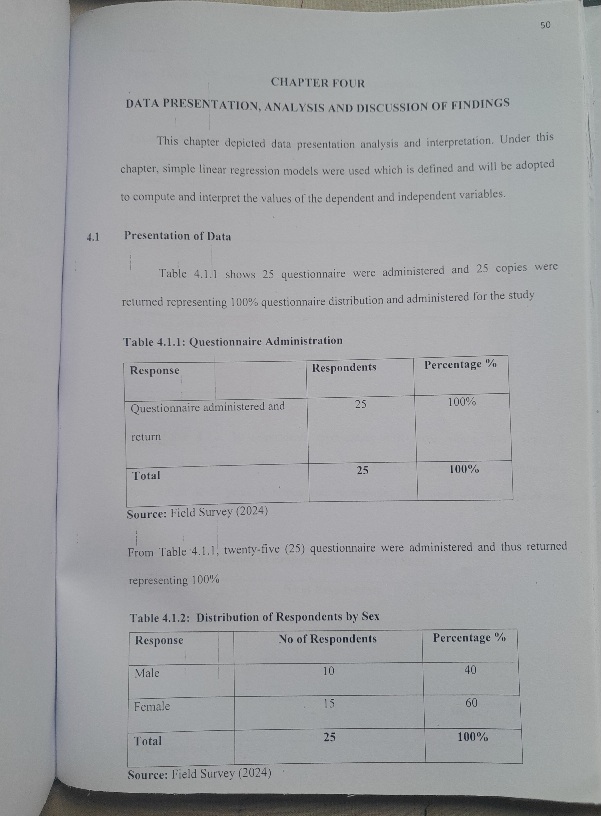

Prevalence of Carbapenemase Production in Pseudomonase Aeruginosa Isolates from Clinical Samples

Prevalence of Carbapenemase Production in Pseudomonase Aeruginosa Isolates from Clinical Samples